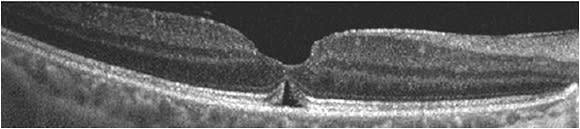

Postoperative OCT findings can also help to explain patients’ VA. Loss of integrity of the ellipsoid zone and outer retina layers can be a limiting factor,4,5 and a decrease in inner macular volume has been shown to correlate with a decrease in VA.6 On the other hand, after hole closure, it is not uncommon for OCT to show a small pocket of subretinal fluid or subfoveal lucency (Figure 2). This generally resolves with time and does not seem to correlate with worse visual outcomes.